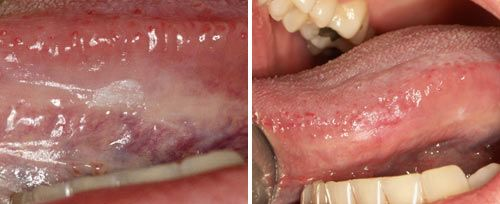

口腔黏膜病治疗

口腔黏膜病:激光照射溃疡面,可充分消毒杀菌,并使其凝结形成硬壳,愈合速度更快;激光也可用于多种类型的着色病损,并促进黏膜上皮再生。

口腔激光怎么治疗口腔特色诊疗——激光治疗_https://www.jmylbn.com_新闻资讯_第12张

激光治疗口腔溃疡前后对比图

口腔激光怎么治疗口腔特色诊疗——激光治疗_https://www.jmylbn.com_新闻资讯_第13张

激光治疗口腔白斑前后对比图

口腔激光怎么治疗口腔特色诊疗——激光治疗_https://www.jmylbn.com_新闻资讯_第14张

激光治疗血管瘤前后对比图

口腔激光怎么治疗口腔特色诊疗——激光治疗_https://www.jmylbn.com_新闻资讯_第15张

激光治疗牙龈色素沉着前后对比图